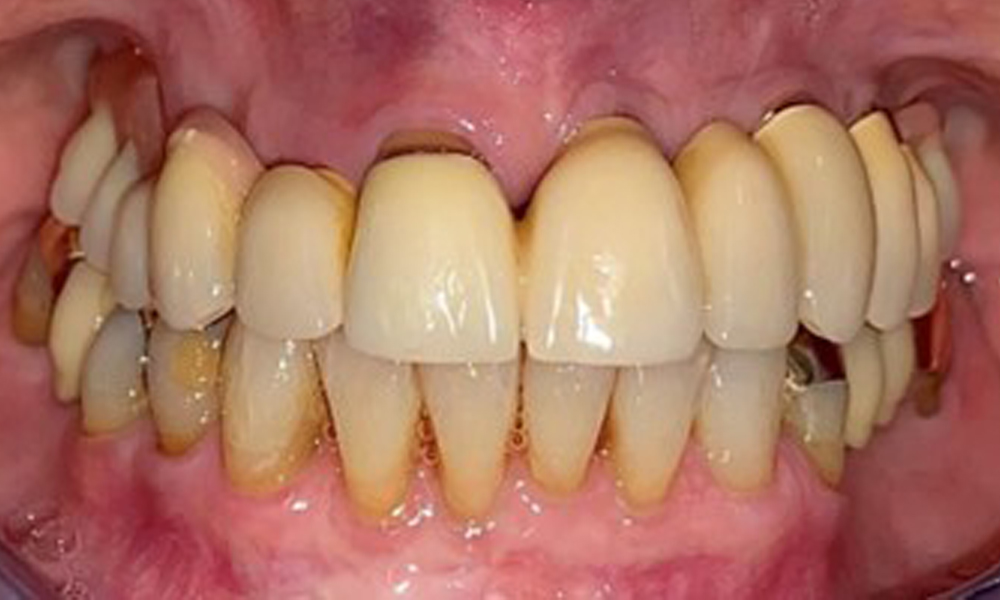

The patient was fitted with a combined removable maxillary telescopic prosthesis more than 25 years ago (Fig. 1, Fig. 2, Fig. 3) and is very happy with her dentures. The patient has an adequate fixed denture for the mandible (Fig. 4).

Frontal view with the maxillary denture in situ.

Fig. 1: Frontal view with the maxillary denture in situ.

The dental findings are as follows: Combined removable implant and tooth-supported telescopic prostheses on implants 15, 13, 21, 23, 24, 25 and tooth 11 (Fig. 1, Fig. 2, Fig. 3). The patient was fitted with a fixed mandibular denture. Adequate bridges were present over 37 to 34 and 45 to 47 (Fig. 4), the crown margins were intact and there were no active caries. A composite filling with a marginal gap was present on tooth 43. There was mandibular gingival recession, exposing 1 to 3 mm of root surface. This also applies to 11.